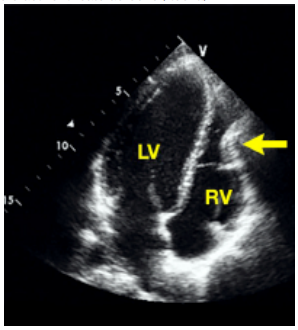

El desplazamiento posterior del esternón provoca una compresión cardíaca. Dado que el ventrículo derecho es la cavidad más anterior del corazón, con íntima relación con el esternón, la mayoría de las alteraciones cardíacas secundarias a PEX afectan principalmente a esta cavidad.

En las Figura 1 y 2, se muestran algunas de las alteraciones estructurales encontradas en pacientes portadores de PEX.